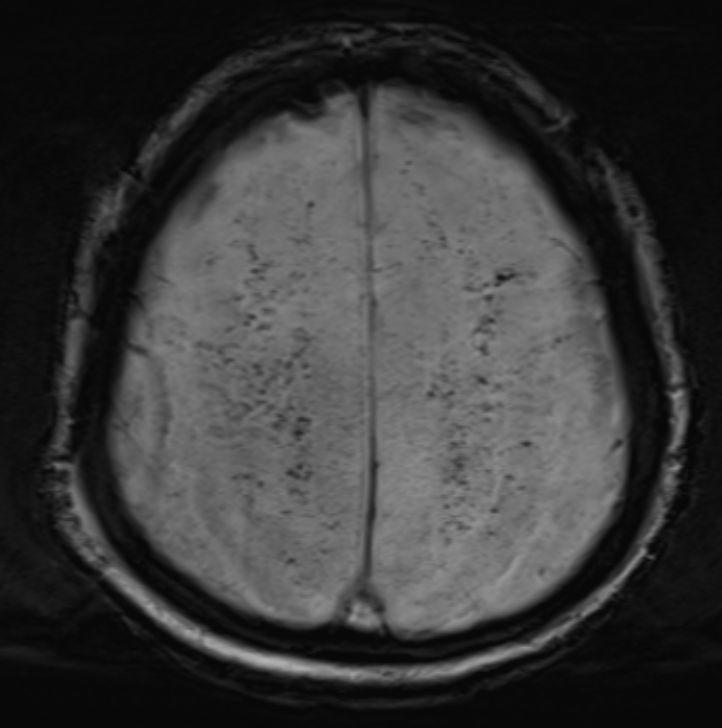

3)SWI(Susceptibility-weighted Imaging)에서 미세출혈 증가

· SWI에서 미세출혈이 잘 보이는 경우가 많음.

· 주로 피질하(subcortical), 시상, 뇌간(Brainstem) 부위에서 점상출혈 형태로 나타남.